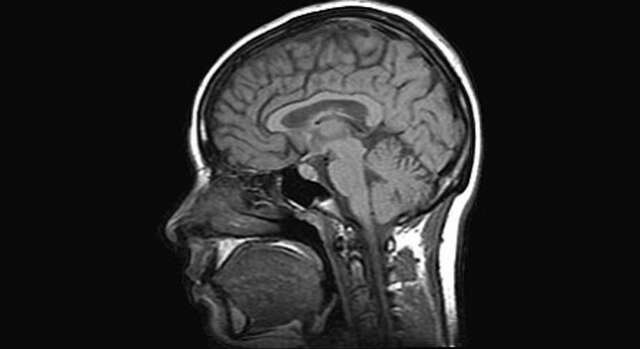

Un grupo de científicos de la compañía médica británica Heptares Therapeutics ha utilizado una de las máquinas de rayos X más potentes del mundo para estudiar la glándula pituitaria, situada en el cerebro, encargada de controlar el estrés la ansiedad e incluso la depresión.

Gracias a este trabajo, se ha hallado una proteina, denominada CRF1, situada en la glándula pituitaria que es la que provoca estos trastornos, según ha recogido The Sunday Times

Los científicos ya sabían que la glándula pituitaria jugaba un papel fundamental en los fenómenos de ansiedad y depresión, mediante la liberación de sustancias químicas a la sangre. Lo que no sabían era que la verdadera responsable de esta perturbacionesera la proteina CRF1, situada en las membranas externas de las células de la glándula.

Fiona Marshall, directora científica de Heptares Therapeutics, ha explicado que “las enfermedades relacionadas con el estrés, como la ansiedad o la depresión, afectan a un cuarto de la población adulta cada año, pero mucha gente desconoce que estas situaciones están controladas por proteínas del cerebro, y una de ellas es la CRF1″.